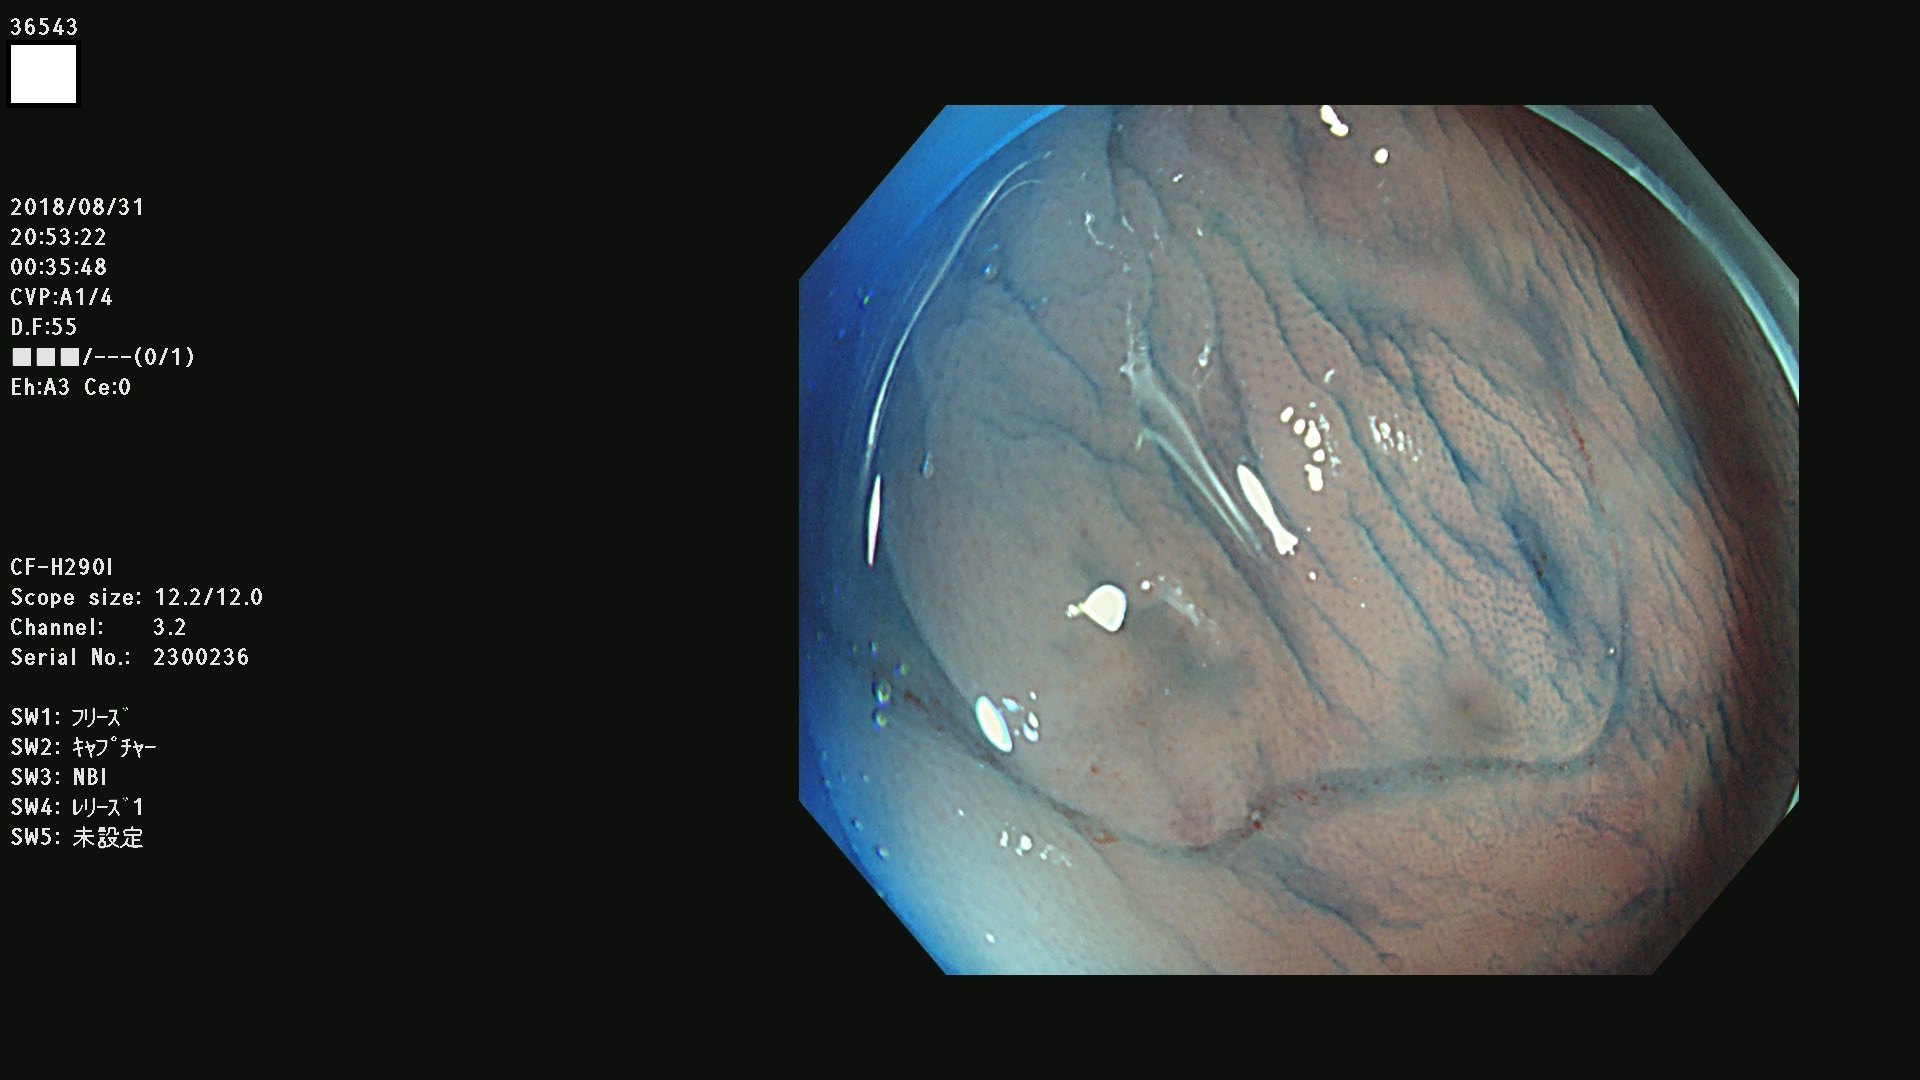

36500 36503 36504 36505 36507(SSAPのみ) 36508 36509 36510 36511 36514 36515 36517 36518 36520 36522(SSAPのみ) 36523 36524 36526 36528 36530 36531 36532 36533 36534 36535 36536 36538 36541 36542 36543 36544 36545 36546 36548 36550 36551 36554 36555 36556 36558 36559 36560 36561 36564 36565 36567 36568 36570 36572 36573 36574 36575 36576 36577 36578 36579 36580 36582 36584 36586 36591 36592 36593 36594 36595 36596 36597 36598

発見困難で危険性の高い平坦型病変(上記100名より抽出)

虫垂SSAP